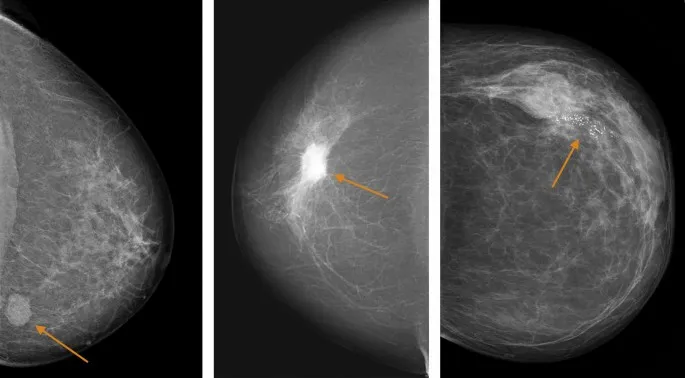

| Breast mammography | Women 50-71 | 3 years | Mammographic density |

| Mammography (50-70y) | 75-85% | 95-97% | 10-15% | 377 (10-year screening) |

| Breast mammography | Women 50-71 | 3 years | Suspicious lesion |